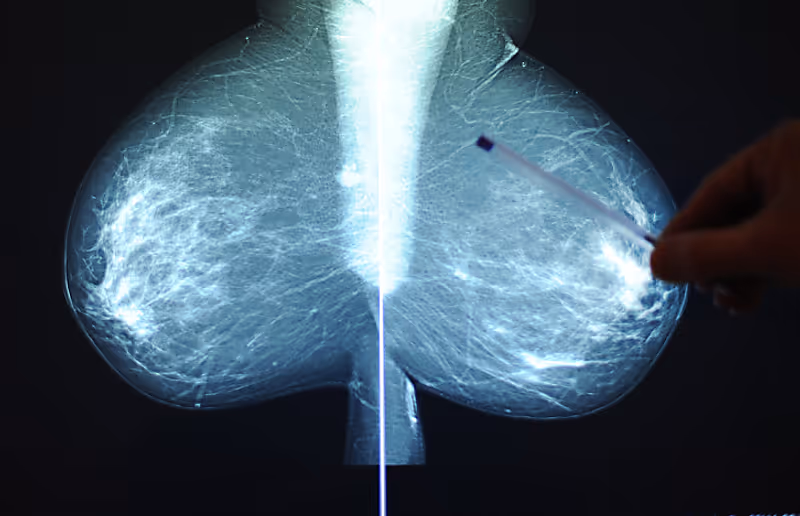

Solche "populären" Anwendungen der Artificial Intelligence sollten aber nicht die Sicht auf die vielen Auswirkungen der Technik auf praktisch alle Aspekte der Patientenversorgung verstellen. Die Radioonkologin: "Künstliche Intelligenz kann helfen, Patientenströme, zum Beispiel zu Untersuchungen wie die Mammografie, besser zu steuern und Wartezeiten zu reduzieren. In der Bildgebung verbessern solche Programme zum Beispiel die Qualität von Mammografie- oder Computertomografie-Bildern. Das erleichtert die Beurteilung von solchen Aufnahmen."

Derzeit herrscht bei der Begutachtung von Mammografien aus dem Brustkrebsscreening jedenfalls das Vier-Augen-Prinzip: Zwei Radiologen führen unabhängig voneinander die Begutachtung durch. "Das ist natürlich ein extremer Aufwand", erklärte die Expertin. KI-Auswertungen könnten hier zunehmend eine Hilfe darstellen. Immerhin seien die Personalressourcen ja überall in der Medizin knapp, würden in Zukunft noch knapper werden. "Maschinelle Unterstützung" bei Routineaufgaben wird wohl immer gefragt sein. "Im Endeffekt muss aber immer ein Arzt die Entscheidung treffen."